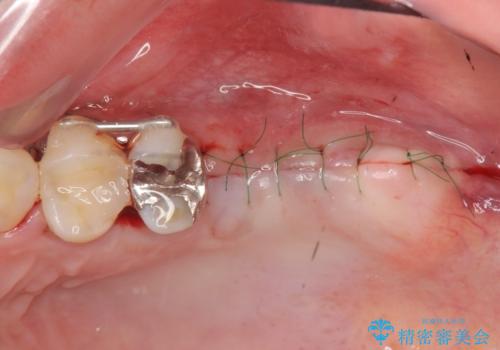

今回は大きく吸収してしまった歯槽骨をしっかりと造成することで、歯間ブラシを行いやすいインプラント周囲環境を整備することができました。